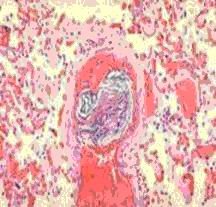

腸道是人體最大的細菌庫,由於腸黏膜自身的保護作用致使細菌和毒素不能入侵,這種保護作用被稱之為防禦屏障。休克、腸缺血、窒息、人工餵養不良等均可導致腸屏障的破壞,進而造成腸道內細菌微生態的失衡以及細菌及毒素的入侵而誘發AHNE。對於AHNE致病性病原體還沒有確切的認識,但從病人的糞便中可分離出厭氧菌、大腸埃希桿菌、特異性的克雷白菌屬、梭狀芽孢或產氣莢膜菌屬以至病毒等,其可導致腸壁感染、壞死、穿孔。糞便中C型產氣莢膜桿菌(產生β毒素的Welchii桿菌)易引起致病作用,造成腸道微循環障礙,而表現斑片狀壞疽性腸道病變。

3、腸屏障功能不全

腸屏障功能包括了機械、免疫、生物、化學及運動功能屏障。在正常情況下腸黏膜上皮細胞、細胞間連線與菌膜構成了機械屏障,且腸道黏液和黏蛋白形成了覆蓋於腸黏膜表面的彈性蛋白層,使細菌不能入侵併對化學和機械性刺激起到保護作用。正常情況下由腸黏膜分泌的分泌型免疫球蛋白(sIgA)對黏膜局部免疫功能極為重要,是為免疫屏障,其作用在於使黏膜表面形成保護層,阻止細菌黏附,使細菌凝集,抑制細菌活動並中和細菌毒素及抵禦病毒,對多種蛋白水解酶。sIgA的缺乏,細菌黏附於黏膜上皮並形成集落,進而造成細菌和內毒素經門靜脈和淋巴系統侵入體循環,形成腸源性內毒素血症和細菌易位(bacteria translocation,BT)。